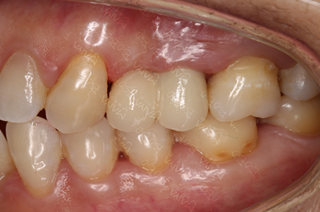

种牙成功后的赵女士

种植完成后的牙齿

种牙成功后口腔ct全景片